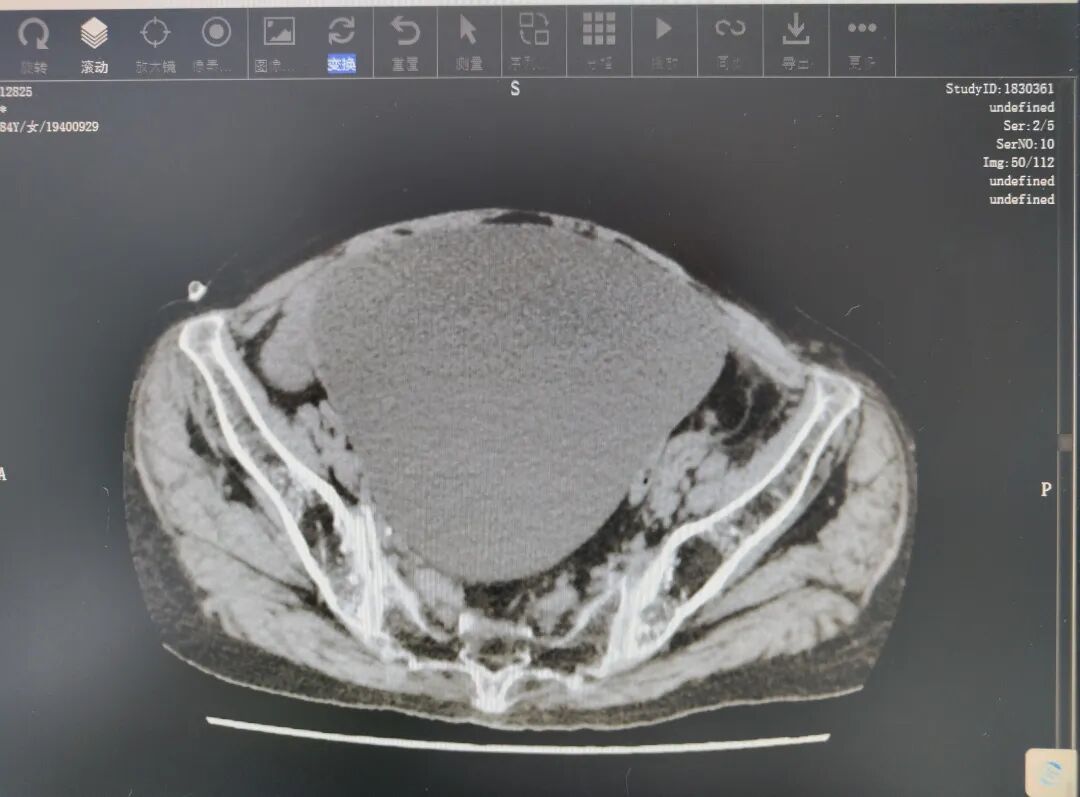

阿婆因“左下腹痛2天”入院,经盆腔CT检查,提示为“盆腔内巨大囊性占位性病变(考虑囊腺瘤)”。考虑到阿婆84岁高龄,且有高血压病史,手术风险显著增加。面对挑战,妇科团队高度重视,迅速组织评估,为阿婆定制精细的手术方案,做好术前准备,力求以最小创伤切除患侧肿瘤,为老人清除健康隐患。

盆腔CT增强扫描显示盆腔内巨大囊性占位性病变